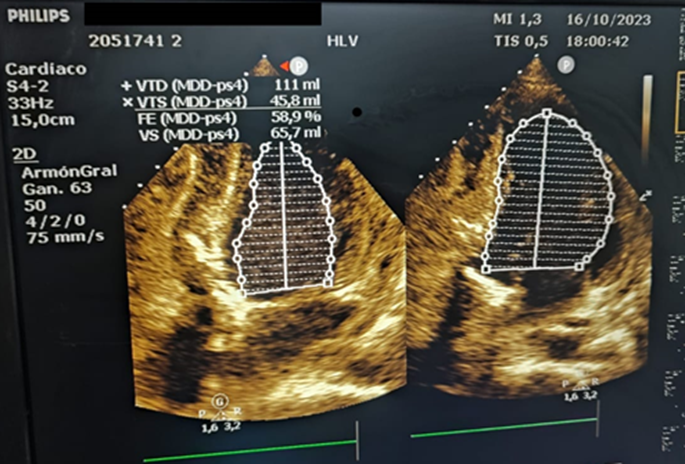

Aproximadamente 3 Semanas posterior al alta presenta cuadro de insuficiencia respiratoria asociado a insuficiencia cardiaca descompensada por lo que acude a nuestro Hospital de Especialidades Abel Gilbert Pontón siendo internada en Unidad Coronaria, a su ingreso se evidencia dolor precordial y torácico bilateral que irradia a región dorsal acompañado de disnea clase funcional NYHA IV/IV, tos persistente y edema leve de miembros inferiores, los laboratorios realizados evidencian anemia leve con hb 10.8 g/dL, péptido natriurético elevado de 12895 pg/ml, enzimas cardiacas negativas, hematuria y proteinuria en uroanálisis; en la radiografía de tórax se muestra cardiomegalia y derrame pleural bilateral; En electrocardiograma taquicardia sinusal, dextrorrotación, complejo QS en cara inferior, sin alteraciones de la onda T y segmento ST. En eco de pleura muestra derrame pleural derecho de moderada a gran cuantía y derrame pleural izquierdo moderado, sospechando de colagenopatía vs enfermedad autoinmune a descartar. Se realiza ecocardiograma transtorácico se evidencia formación aneurismática del VI de 9.5cm x 9.7cm tapizado por trombos con pérdida de la continuidad a nivel perimembranoso septal, además de una miocardiopatía dilatada con FEVI (fracción de eyección del ventrículo izquierdo) 28%. El estudio de líquido pericárdico da como resultado exudado con relación líquido/sérica de LDH 1,8 y proteína 0,7. En ecocardiograma transesofágico (Ilustración 1,2,3) se confirma pseudoaneurisma de gran tamaño del VI en región basal posterior con flujo bidireccional de 10 cm x 7,22cm tapizado de formación trombótica con pérdida de la continuidad de la región basal y posterior del VI con hipocinesia global e hipertensión pulmonar leve con insuficiencia mitral y tricuspidea leve por lo que se decide resolución quirúrgica.

Ilustración 1 Ecocardiograma Transesofágico. Pseudoaneurisma del VI en su porción septal

Fuente: Hospital de Especialidades Guayaquil “Doctor Abel Gilbert Pontón”.

Autor: Dra. María Sánchez Sánchez.

El tratamiento consistió en reparación quirúrgica del pseudoaneurisma usando parche de Dacron para tapizar el sitio de ruptura miocárdica cubriendo parte del septum y segmento posterior, se realiza ecocardiograma transquirúrgico.

Ilustración 6 Evidencia mejoría inmediata de la FEVI 58%.